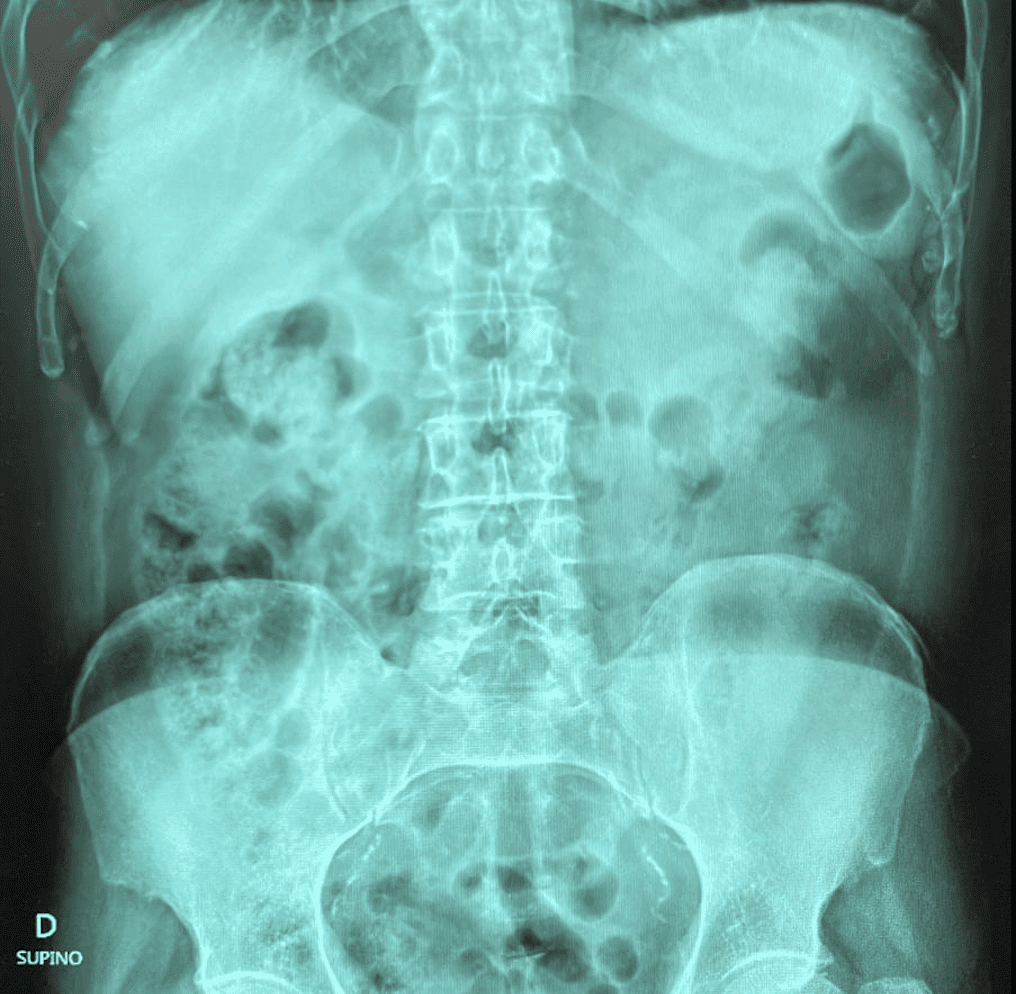

Como pruebas complementarias se realiza ECG con ritmo sinusal, una analítica de sangre con perfil hepatopancreático y TNT normales, y una gasometría donde destacan acidosis e hiperlactacidemia. Como prueba de imagen se realizan radiografía de abdomen sin otras alteraciones.